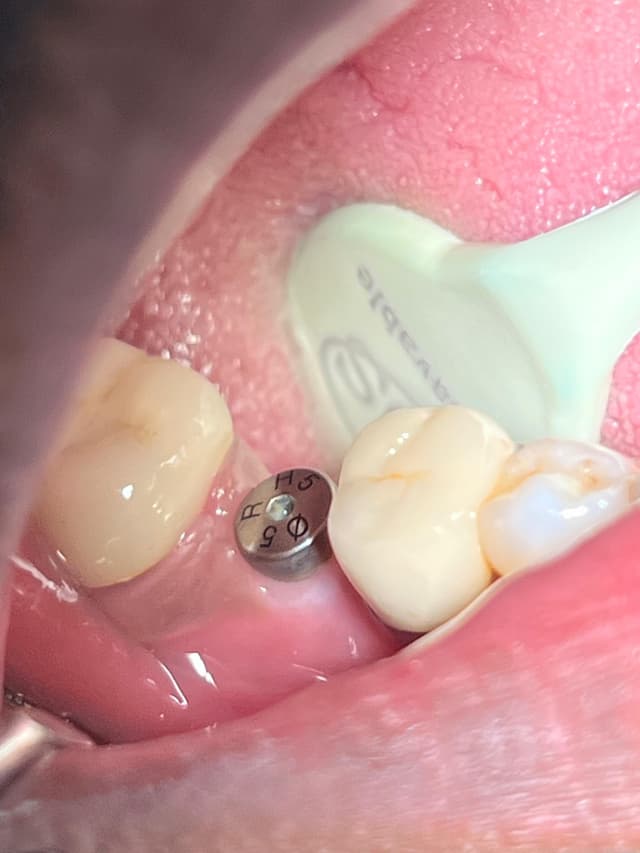

Gallery

Root canal treatment